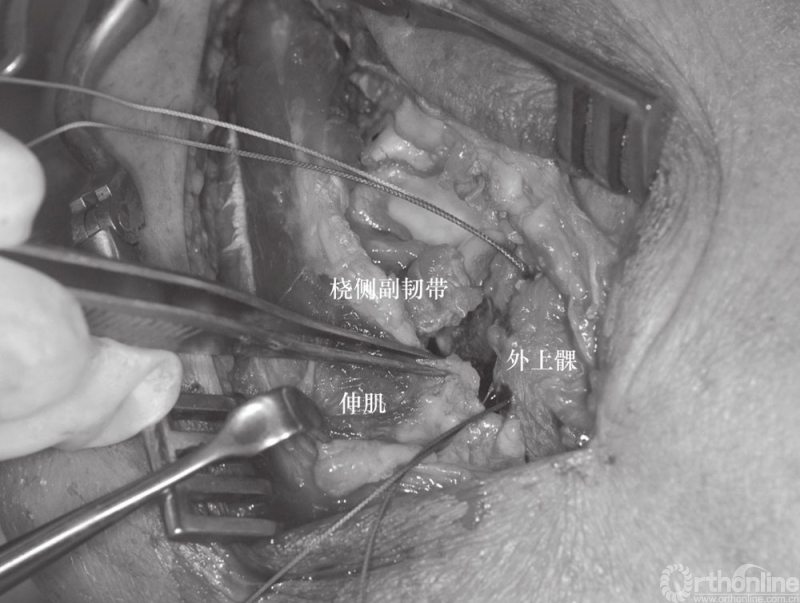

(2) 患者采用全麻、侧卧位,入路采用外侧入路,该入路便于切开复位、暴露肘关节、桡骨头重建和置换、固定冠状突以及后外侧韧带复合体的修复。外侧皮肤切口以肱骨外上髁为中心。前臂保持旋前位以增大骨间后神经与手术区域的距离。与单纯的桡骨头骨折采用的经肘肌和尺侧腕伸肌间的Kocher's间隔入路不同,对“恐怖三联征”患者可以利用损伤本身所造成的间隙进行暴露,而不需要特意的切开关节囊。损伤本身会导致关节囊、桡侧副韧带及大部分外侧肌肉软组织的破坏(图3)。

图4 该损伤出现关节囊、桡侧副韧带及外侧肌肉软组织损伤(⋆桡骨头切除后)

如果伸肌总腱止点损伤应进行修复,Kocher's间隙的筋膜也应修补(图9和图10)。如果在修复桡骨头及外侧副韧带后,肘关节屈曲40°以上仍发生半脱位,则还需经内侧入路,以同样方法修复内侧韧带复合体(图11)。